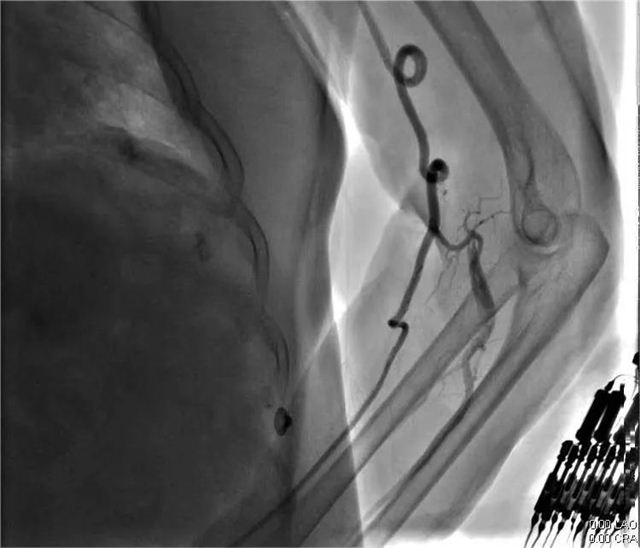

一面锦旗,不仅仅代表患者对疾病治疗效果的认可,更是对医护团队的认可。近日,年过八旬的逯奶奶和其家属将一面写有“精湛医术出妙手 体贴入微胜亲人”的锦旗送入长治市第二人民医院心血管内科医护人员手中,表达了患者对心血内科全体医护人员的感激之情。 患者家属说:“我母亲经过冯翠萍主任、王涛医生以及全体护理人员的积极治疗、精心护理,病情逐渐好转并康复出院。他们严谨、细心、热情的工作精神,精湛的医学技术,让我和我的家人非常感动和十分敬佩,非常感谢心血管内科全体医护人员,千言万语难表内心真情,唯有送上锦旗表示感谢。” 医术精湛 精心 患者逯奶奶已年过八旬,2023年11月发病至今的半年多时间里,多次因心肌梗死、心力衰竭,也多次就诊于我市多家医院;今年5月患者再次出现心绞痛症状,发作频繁,无法耐受,逯奶奶为求诊治就诊我院心血管内科进一步治疗。 入院后,主管医师王涛仔细询问病史并为其进一步进行检查。患者逯奶奶由于年岁已高,基础性疾病较多,既往曾在外院行冠脉造影术,血管扭曲,风险大。心血管内科主任冯翠萍、主管医师王涛再次为患者评估,患者为高龄,冠脉入路血管扭曲严重,手术风险极高;重新评估冠脉手术操作入路,因右桡动脉入路无法到达右冠,股动脉闭塞、狭窄无法进行穿刺,最终选择从左桡动脉进行手术。术中逯奶奶左侧动脉扭曲严重,在孙涛教授指导下,顺利找到罪犯血管,狭窄最重处达到99%,给予支架治疗,术后在心血内科医护人员的精心治疗和护理下,逯奶奶未再出现心绞痛发作,顺利康复出院。 冯翠萍主任亲切的说:“锦旗是赞许、是荣誉,更是对我们的鼓励和鞭策,一面锦旗承载着患者对医院的信任和感激,象征着医患情深,长治二院心血管内科团队将以此为动力,更加努力地为每一位患者提供更优质的诊疗方案及服务。” 病情分析 左侧动脉严重扭曲 右冠为罪犯血管,第一转折处节段性狭窄90-99% 右冠植入1枚支架术后,未见残余狭窄 科 长治市第二人民医院心血管内科成立于2011年1月,是长治市市级重点专科,是以临床药物治疗、心脏介入、心脏功能评估、心脏康复为主要手段,集临床、科研、教学、预防、康复为一体的综合性心血管专科。 心血管内科现有医护人员26人,其中硕士研究生4人、主任医师1人、副主任医师1人、主治医师6人、住院医师2人、副主任护师1人、主管护师3人、护师(士)8人。目前科室开放床位30张,重症监护病房(CCU)床位8张。科室能够诊治疾病有:冠心病、各种心律失常、心脏瓣膜病、心肌病、心肌炎、心力衰竭、高血压、肺栓塞、下肢静脉血栓等各类常见及疑难心血管疾病。常年开展常诊、急诊冠脉造影及支架植入术,各种心律失常的射频消融术,心脏起搏器植入术,先天性心脏病介入封堵术。 心血管内科培养了一支专业技术过硬、团结进取、勇于创新的心血管疾病诊疗团队,全科医护人员以“医者仁心、救死扶伤”竭诚为广大心血管疾病患者提供最优质的医疗服务。 咨询热线 长治二院心血管内科 0355—3126031 冯翠萍主任 18603550120 王涛医生 18635550969 编 辑丨卞 晨 审 核丨雷 赫